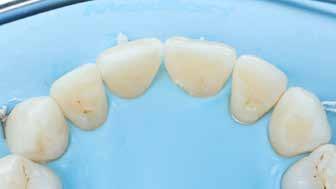

A cikkünkben bemutatásra kerülő eset ellátása során preparációt héjak készre vitele során a platinafólia technikát alkalmaztuk.

kívül vékonyak, és ezáltal a végleges rögzítésük előtt jelentős olyan minimál invazív kezelési eljárásnak számítanak, amely

elérni. A fent leírtak alapján bátran

preparációt nem igénylő héjak készítése mellett döntöttünk. A alkalmaztuk. Annak ellenére, hogy az elkészítésre kerülő héjak rendjelentős törésveszéllyel állunk szemben, összességében mégis amely segítségével kifogástalan esztétikai eredményeket lehet javasoljuk e módszer alkalmazását.